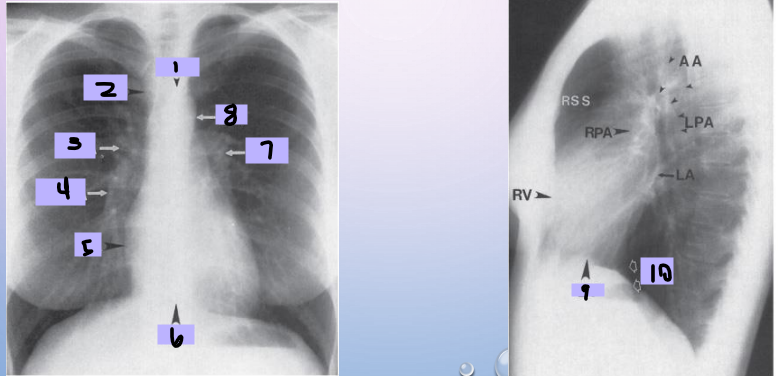

Aortic arch

#1

Superior vena cava

#2

Right pulmonary artery

#3

Right descending pulmonary artery

#4

Right atrium

#5

Right ventricle

#6

Left pulmonary artery

#7

Descending aorta

#8

Left ventricle

#9

Inferior vena cava

#10